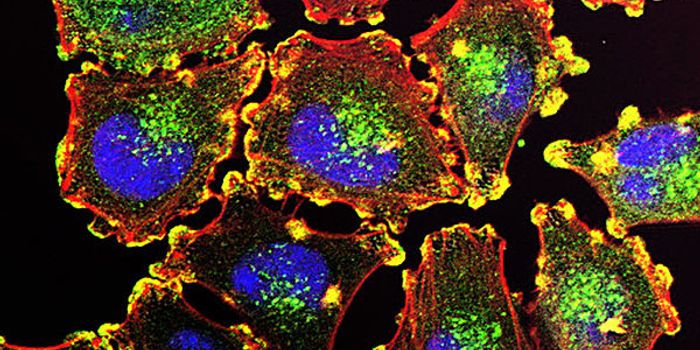

APR 24, 2015Cell & Molecular BiologyResearchers from the Universitat Autònoma de Barcelona (UAB) Department of Cellular Biology, Physiology, and Immunology, ...

AUG 31, 2021Clinical & Molecular DXCellular stains are organic fluorescent dyes or fluorescent conjugates designed to localize to a specific organelle or c ...